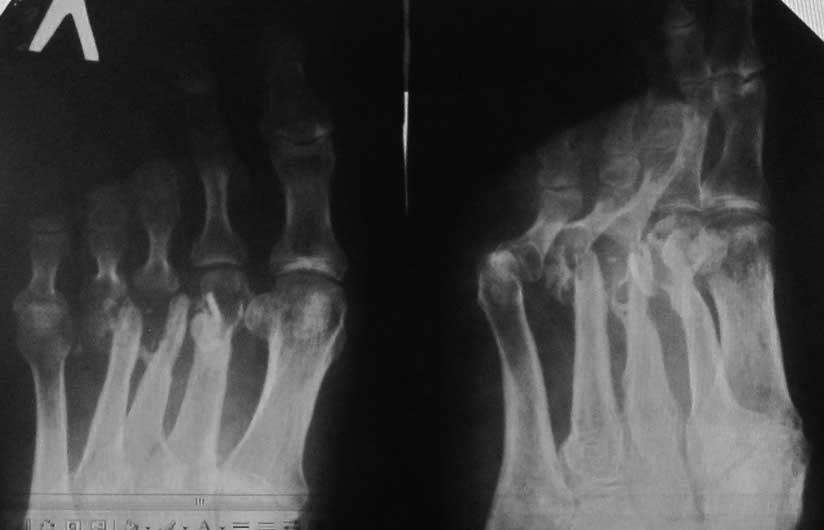

Больной 45 лет, мужчина. Оперирован спицами в мае 2013 года в Таджикистане по поводу открытых переломов 2-4 плюсневых костей. Спицы были удалены со слов больного через 2 недели, после чего он был выписан на амб. долечивание, приступил к дозированной нагрузке. В сентябре 2013 года открылся свищевой ход на тыле стопы в 3-м межплюсневом промежутке. Больной лечился самостоятельно различными антибиотиками. Рассматривается секвестрнекрэктомия головок и части диафизов 2-4 плюсневых костей, проточно-промывное дренирование+спейсер с ванкомицином (или без спейсера), а затем в холодном периоде – костная аутопластика.Возможно после секвестрнекрэктомии появится избыточная подвижность 2-4 пальцев – чем и как посоветуете фиксировать??